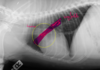

label

larynx